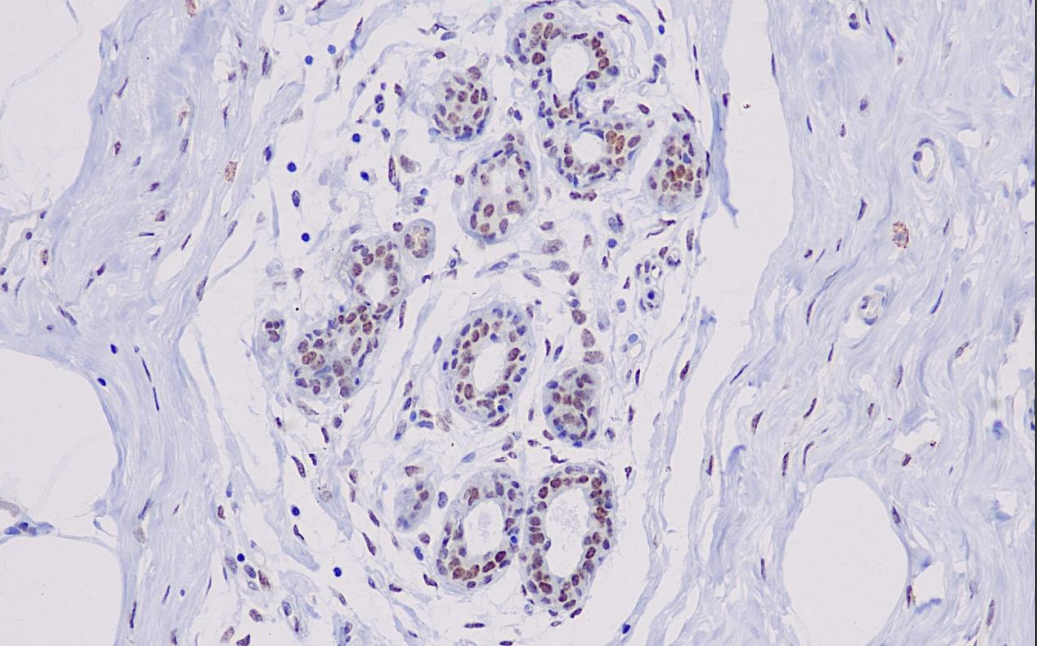

Cellular localization: nucleus

Positive control: mammary gland

The BRCA1 gene is located at 17q21 and encodes a protein consisting of 1,863 amino acids. According to research, about 5% to 10% of breast cancers are hereditary, and these familial breast cancers are often accompanied by mutations in the BRCA1 or BRCA2 genes, with mutation rates as high as 30% to 50%.Loss of function of BRCA1 increases the susceptibility to breast and ovarian cancer. This antibody is mainly used in breast and ovarian cancer research.

BRCA-1 Antibody Reagent binds specifically to the BRCA-1 molecular antigen. Immunohistochemistry kits containing BRCA-1 Antibody Reagent are suitable for the precise diagnosis of hereditary breast and ovarian cancers and so on.